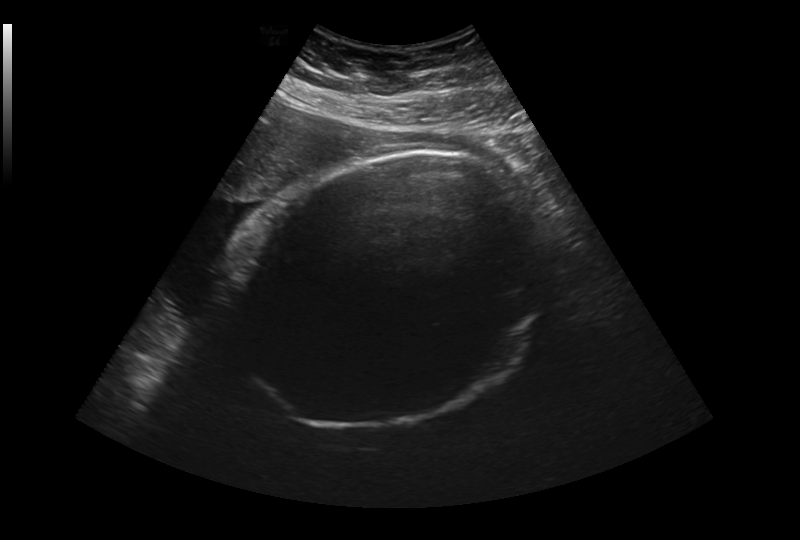

The code parses through over 300 images of different prenatal photos using computer vision technology. We are able to identify prenatal heads.

We built it using python and Open CV. We were able to blur and sharpen the images in order to hone in on the specific portions we wanted to find in order to attempt to measure the babies head shapes.

We are proud of the fact that we were able to identify the fetal heads while they were in the womb, even with the image quality being so low.